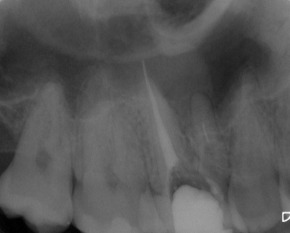

Nach erfolgter Information über die vermutete Prognose unternehmen wir den Versuch, das frakturierte Instrument darzustellen. Nach Entfernung der Aufbaufüllung werden die Kanaleingänge dargestellt (Abb. 2). Es zeigt sich, dass neben dem distovestibulären Kanal auch ein vierter Kanal (mb2) vorhanden ist. Die Darstellung der Wurzelkanaleingänge erfolgt in unserem Haus mit dem Aufsatz 1R des Tigon+. Dank der Abwinkelung des Instruments profitiert man von einer sehr guten Sicht auf die Behandlungsstelle. Zudem erlaubt es ein schnelles und gezieltes Abtragen von Dentin, ohne dabei den Zahn unnötig zu schwächen.